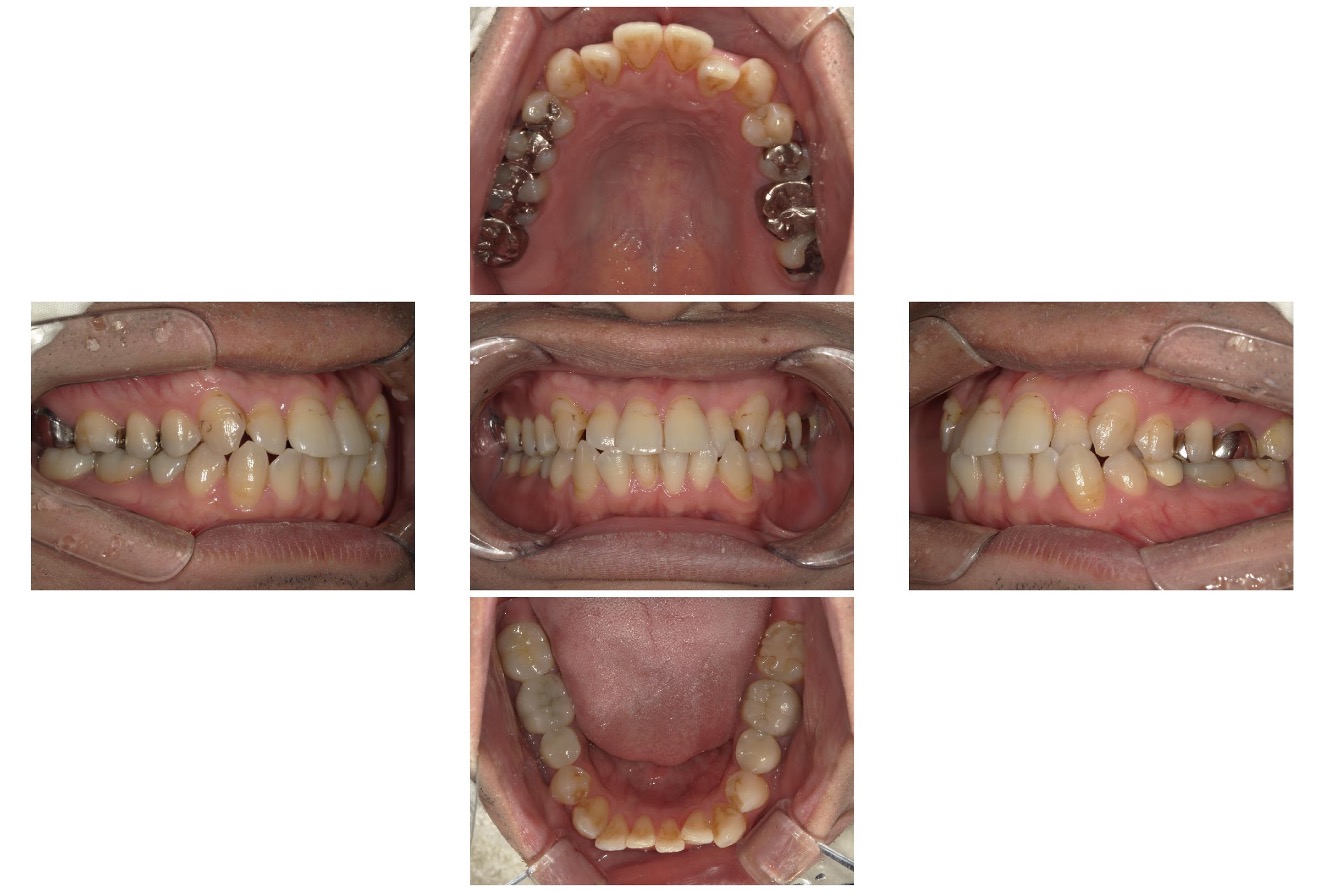

Case.02

治療前

治療後

| 主訴 | 上も下も凸凹してるのが気になる |

|---|---|

| 治療 期間 | 2年4カ月 |

| 治療費 | 880,000円 (税込968,000円) |

| 治療 内容 | インビザライン・顎間ゴム |

| 治療の リスク | 1日に20時間以上装着しないと、予定通りに歯が動かないことがあります。 装着後数日痛みがあります。 |